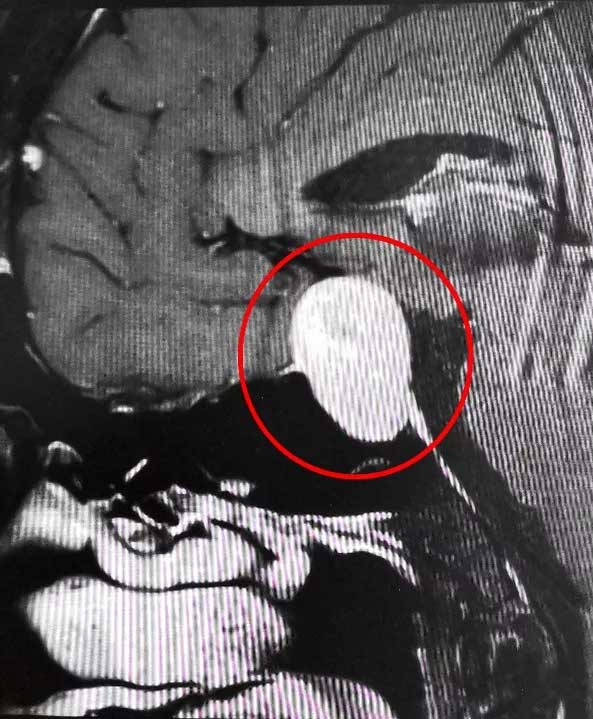

近期,上海蓝十字脑科医院6B病区收治了这样一位典型患者。一位男性垂体瘤患者,患者一年前出现视物模糊情况,起初他以为是眼睛问题,但是到医院眼科检查时未查出明显异常。来院后经检查,患者双侧视野缺损,后经医院MR检查确诊为3公分垂体巨大腺瘤。患者手术指征明确,无明显手术禁忌,在征得家属同意后,李士其教授在吴治群博士协助下经蝶窦入路成功为患者进行了手术,显微镜下将鞍内肿物切除。经过十余天恢复,目前患者已顺利出院。

▲ 垂体巨大腺瘤超蝶鞍生长